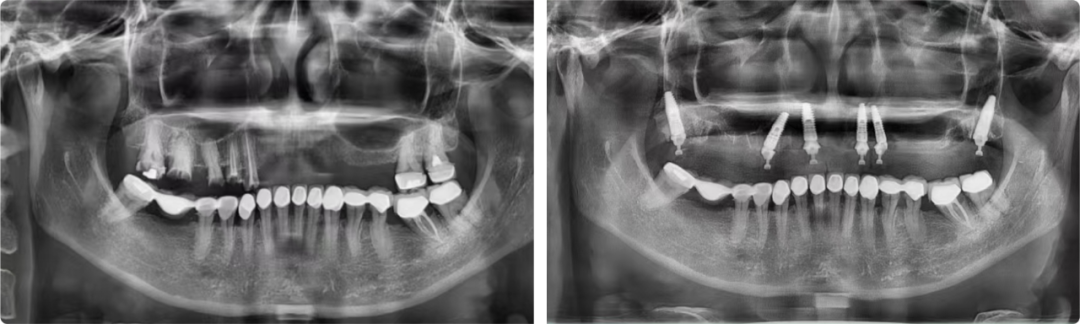

做完CBCT检查,张洁发现患者的情况非常棘手:牙槽骨骨量不足、骨质疏松,能选择的种植点位非常有限且靠近上颌窦,种植体容易穿透,造成种植失败。张洁为患者精心制订了All-On-6半口即刻负重穿翼种植手术方案,这个方案难度很高,但效果最为理想。

患者术前术后全景片

事实证明,手术难度超出预期:拔第一颗牙就发现有粘连,牙槽骨存在慢性炎症,而这个点位是准备做穿翼板种植的。“这种情况真是雪上加霜!每一颗我都做得非常谨慎,需要把手感发挥到极致,但凡有一颗种不上,手术到此结束,整个治疗方案就会失败!”术中,张洁不断提醒自己再细一点,手感再好一点。

这台手术历时三个半小时,比平时多花了一倍多时间,所幸的是六颗种植体全部成功负重。术后,患者顺利戴冠,咬合良好。